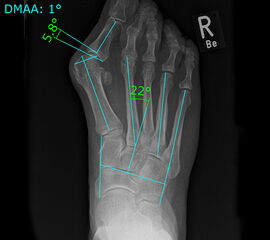

• Folgende Winkel können präoperativ zur Erleichterung der Planung am Röntgenbild eingezeichnet werden:

• IMW (Intermetatarsalwinkel).

• HVW (Hallux valgus-Winkel).

• DMAA (Distal Metatarsal Articular Angle) – Planung der ggf. notwendigen Reverdin-Isham-Osteotomie.

• PPAA (Proximal Phalangeal Articular Angle) – Planung der ggf. notwendigen Akin-Osteotomie.

• VAW (Vorfußadduktionswinkel) – Planung der Ausrichtung der DMMO (Distalen minimalinvasiven Metatarsale Osteotomien).

Einschränkend ist anzumerken, dass o.g. Winkel projektions- und rotationsabhängig sind 15. Daher ist intraoperativ die Planung anhand von Bildverstärkeraufnahmen zu verifizieren und ggf. anzupassen.

Zum Lesen der Bildbeschreibung und zur Vollansicht bitte das Bild anklicken.

In unserer prospektiven Studie wurden 10 Patienten (8 Frauen und 2 Männer; Ø Alter 58 ¼ Jahre) mit einem symptomatischen Hallux valgus bei Pes adductus und Metatarsalgie mittels einer Lapidusarthrodese und einer lateralisierenden DMMO versorgt. Die Fusion des TMT-I-Gelenkes erfolgte offen mittels einer winkelstabilen, plantaren Platte. Alle zusätzlichen distalen Eingriffe (DMMO, Isham-OT, Akin-OT, Kleinzehenkorrekturen) wurden in minimalinvasiver Technik durchgeführt. Die Patienten wurden nach 6 Monaten klinisch und radiologisch nachuntersucht.

Der präoperative AOFAS-Score betrug 41,5 Punkte und konnte postoperativ auf durchschnittlich 86,2 Punkte verbessert werden (p<0,005). Der IMW reduzierte sich von Ø 16,7° (8,5°-20,3°) präoperativ auf Ø 7,14° (6,1°-9,5°) (p<0,005). Ebenso konnte der HVW von präoperativ Ø 45,2° auf postoperativ Ø 9,4° (p<0,005) korrigiert werden. Durch die Durchführung der modifizierten, lateralisierenden DMMO veränderte sich der präoperative VAW von Ø 23° (19,3°-33,5°) auf Ø 15,6° (13°-17,2°; p<0,004).